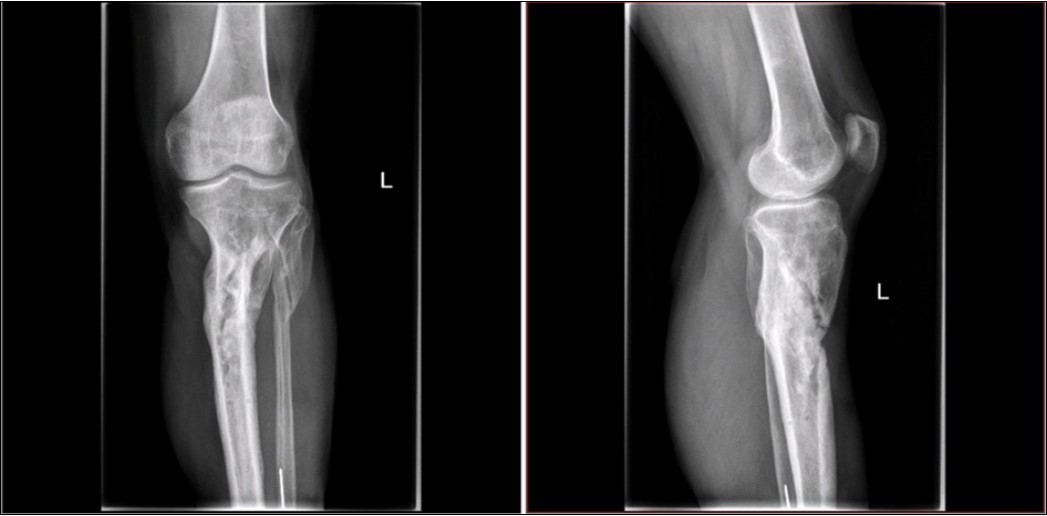

Figure 3.22 January – primary X-ray oblique splinter fracture of the tibia shaft

Figure 5.22 January – primary X-ray - Fracture stabilization using external fixator

Figure 6.22 January – primary X-ray - Fracture stabilization using external fixator

Figure 28.23 April. Surgery conversion of osteosynthesis. Removal external fixator and implantation intramedullary tibial nail. Gradual bone healing - last X-ray september 2019

Figure 29.23 April. Surgery conversion of osteosynthesis. Removal external fixator and implantation intramedullary tibial nail. Gradual bone healing - last X-ray september 2019